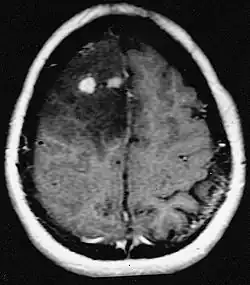

![]() Glioblastoma arising in an astrocytoma. This spinal cord exhibits both a lightly staining microcystic astrocytoma as well as a darkly staining glioblastoma. | |